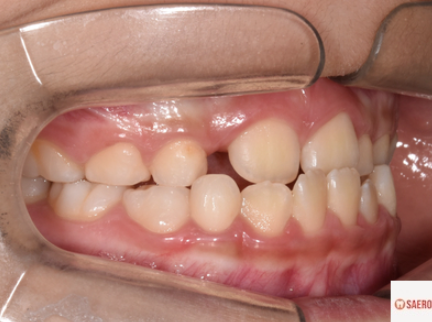

왼쪽이 교정 전 오른쪽이 교정 후입니다.

d1d86fa678bc9afe4b079fc3bd0a6047_1743648137_3193.png

정상적인 앞니 덮임을 보여주고 있습니다.

앞니 뿐만 아니라 작은어금니와 큰어금니에서도

정상적인 치아 덮임을 보여줍니다.